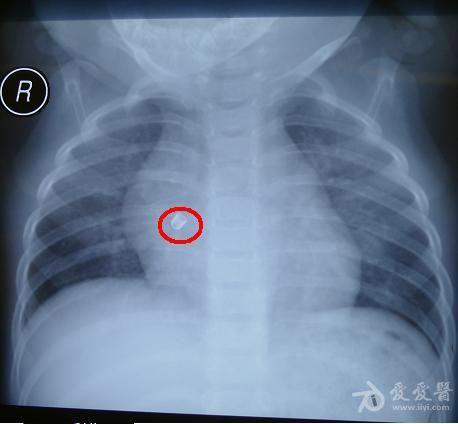

看胸片说诊断气管异物

胸片?